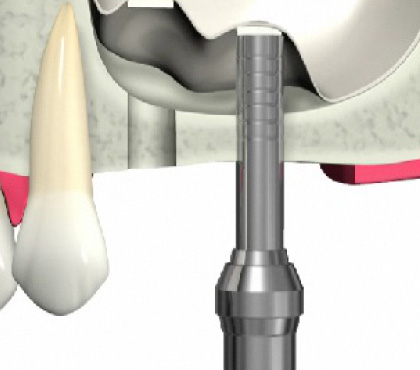

ソケットリフト方法

歯肉を切開します。

骨をドリルで切削します。

上顎洞の壁を押し上げます。

骨の材料を充填します。

インプラントを埋入します。